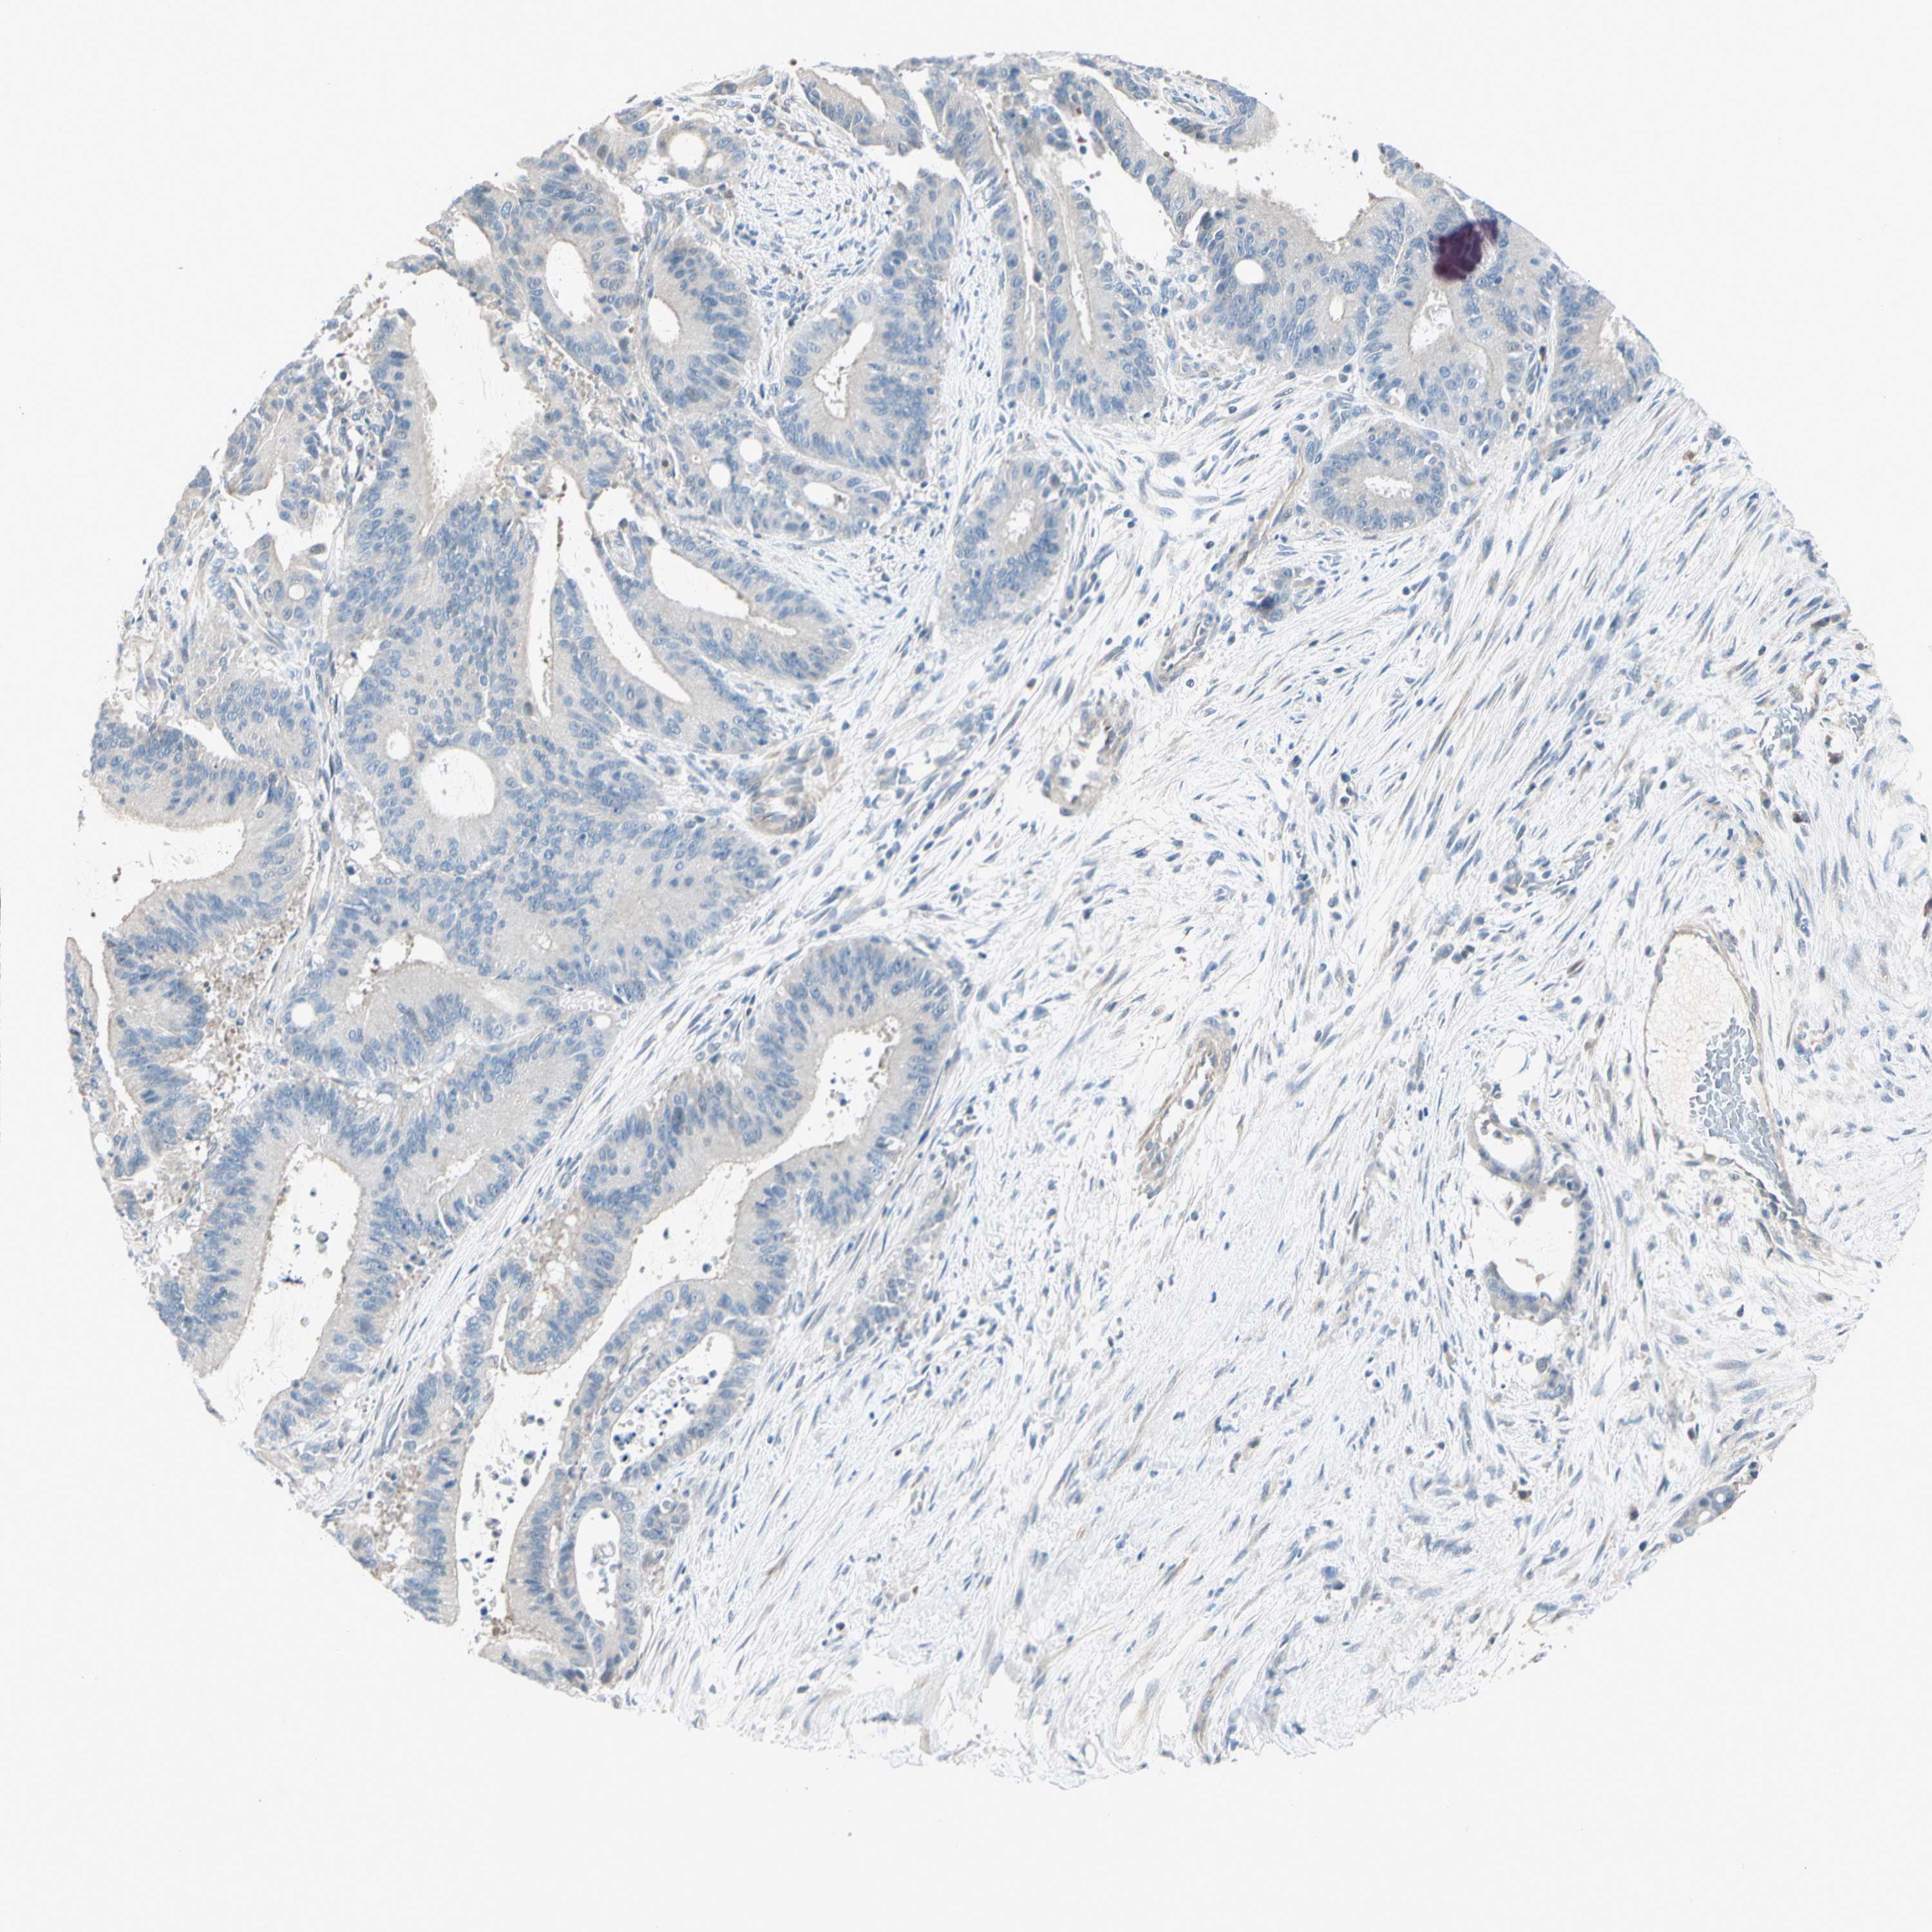

LIVER CANCER - Protein expressioni

A mouse-over function shows sample information and annotation data. Click on an image to view it in a full screen mode. Samples can be filtered based on level of antibody staining by selecting one or several of the following categories: high, medium, low and not detected. The assay and annotation is described here.

Note that samples used for immunohistochemistry by the Human Protein Atlas do not correspond to samples in the TCGA dataset.

Antibody stainingi

Antibody staining in the annotated cell types in the current human tissue is reported as not detected, low, medium, or high, based on conventional immunohistochemistry profiling in selected tissues. This score is based on the combination of the staining intensity and fraction of stained cells.

Each image is clickable and will lead to virtual microscopy that enables deeper exploration of all samples and also displays staining intensity scores, fraction scores and subcellular localization as well as patient and tissue information for each sample.

Antibody HPA009128

Antibody HPA029564

Staining

High

Medium

Low

Not detected

Intensity

Strong

Moderate

Weak

Negative

Quantity

>75%

75%-25%

<25%

None

Location

Nuclear

Cytoplasmic/membranous

Cytoplasmic/membranous,nuclear

Cholangiocarcinoma

Carcinoma, Hepatocellular, NOS